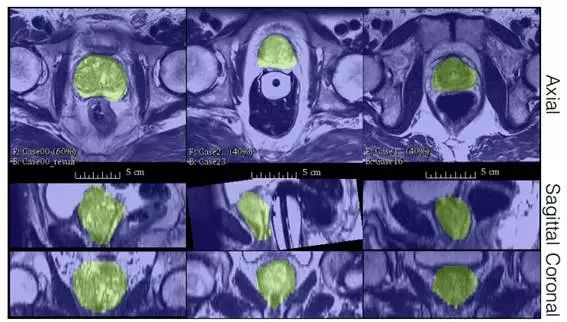

2018年德国医疗康复机构提出一种具有代表性的基于全卷积的前列腺图像分割方法。用CNN在前列腺的MRI图像上进行端到端训练,并可以一次完成整个分割。提出了一种新的目标函数,在训练期间根据Dice系数进行优化[15]。通过这种方式,可以处理前景和背景之间存在不平衡的情况,并且增加了随机应用的数据非线性变换和直方图匹配。实验评估中表明,该方法在公开数据集上取得了优秀的结果,但大大降低了处理时间。

图7 PROMISE 2012数据集分割结果。